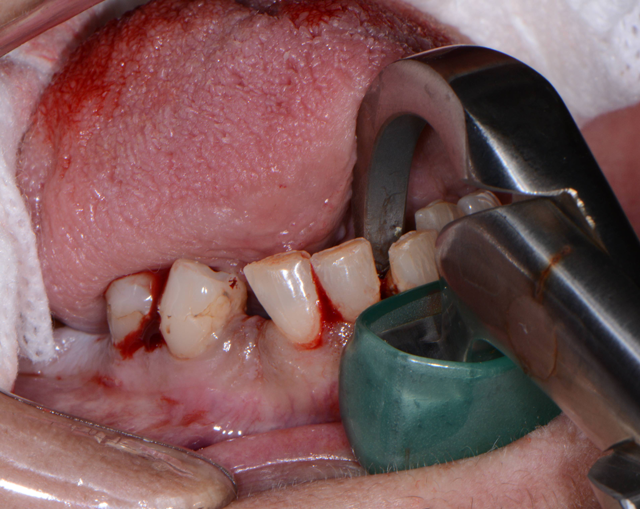

Starting in the maxillary arch, the teeth were extracted using the Physics Forceps (GoldenDent). The Physics Forceps act simply like a Class I lever, where only one force is applied with the beak on the lingual aspect of the tooth. Once the beak is placed at the lingual cervical portion, the soft bumper is placed on the buccal alveolar ridge at the approximate location of the muco-gingival junction to balance the beak. The beak grasps the tooth, while the bumper is the fulcrum to provide leverage and stability for the beak. Extraction is accomplished with wrist movement rotation in a buccal direction, which is usually accomplished within 30 to 60 seconds depending on the tooth morphology.

Once the teeth in the maxillary arch were removed, any granulation tissue remaining within the sockets were removed using a curette and any sharp areas of the alveolar crest were leveled with a bone bur (Komet USA) and smoothed with a bone file (GoldenDent) (Fig. 4).